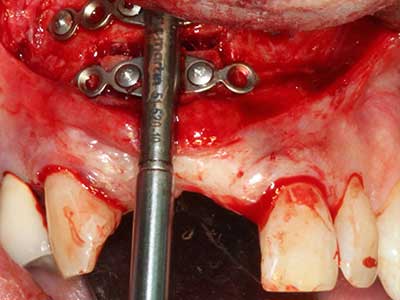

Пиезохирургията има допълнителни предимства при събиране на костни блокове. В допълнение към високата прецизност при остеотомията, описана по-горе, употребата на фините режещи накрайници значително намаляват загубата на материал. Голяма загуба на материал по време на събиране може да се очаква с дебелите накрайници, особено при употреба на борери Линдеман (Lakshmiganthan, Gokulanathan et al. 2012). Базалното разделяне, което е необходимо, особено за присадка на блок при ретромолар, е улеснено от специално създадени правоъгълни триони. В резултат на това, пиезохирургията е разглеждана като прецизна, улеснена и безопасна процедура за събиране на костни блокове в ретромоларното пространство (Happe 2007) (Фиг. 1-12).

Индикация: Костно разделяне/ шиниране?

Костната тъкан е не само минерализирана структура, тя съдържа и съществено количество колагенови влакна. Това означава, че тя има не само добра компресивна сила, но и известна степен на гъвкавост, която може да се възприеме като предимство при извършване на костна аугментация. В класическата процедура по разширяване чрез костно разделяне, атрофиралият алвеоларен гребен е разделен надлъжно и внимателно разширен след достигане на подходящата остеотомна дълбочина (Фиг. 13-16), в идеалния случай без допълнително отстраняване на периостеума (Brugnami, Caiazzo et al. 2014, Stricker, Fleiner et al. 2014). Системите с винт и пластини с увеличаване на разстоянието при разширяване са доказали ефективността си при разделяне на двете костни ламели, оставайки под прага на фрактурите. В общи линии, оставащата ширина на костта от поне 3–4 mm е задължителна (Chiapasco, Zaniboni et al. 2006), за да се гарантира добра гъвкавост и достатъчно костно покритие за бъдещото поставяне на импланти. Ако е необходимо, вертикалната остеотомия на едната или двете страни може да подобри гъвкавостта. Комбинацията с допълнителни техники за аугментация, особено в букалната страна, е описана като алтернатива на класическата техника.

Процедурата по разделяне е атравматична и няма голяма загуба на пространство, използвайки пиезотриони, и няма значителна разлика между импланти в разделени челюсти и импланти в алвеоларния гребен без костен дефицит (Chiapasco, Zaniboni et al. 2006, Danza, Guidi et al. 2009). Въпреки това, важно е да има достатъчно и продължително охлаждане, особено при ограничено и дълбоко разделяне, за да се избегне термичен стрес в апикално-остеотомните зони.